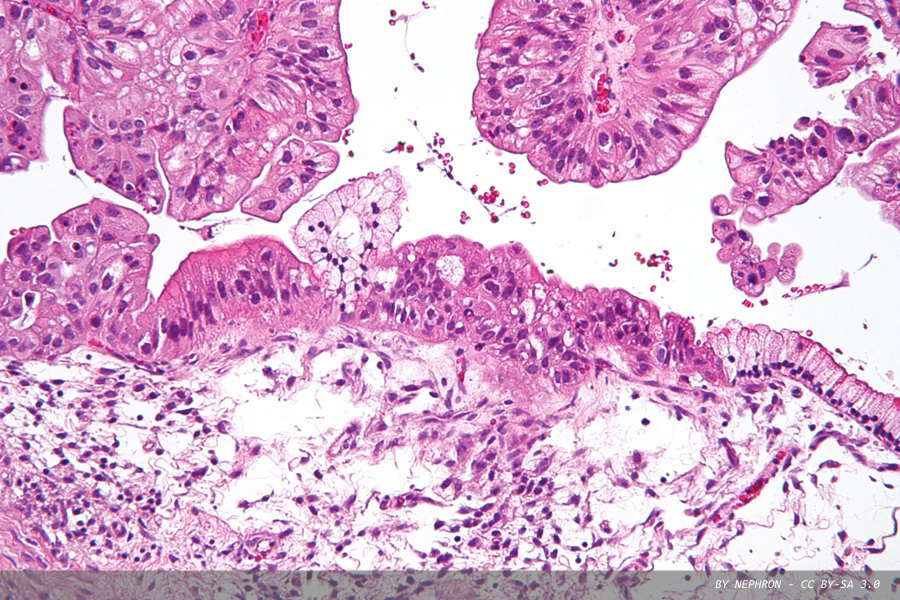

The therapy is designed to destroy both cancer cells and cancer‑associated fibroblasts – supportive cells inside the tumour that help it grow and protect it from the immune system. By breaking down these cells, the treatment may make tumours more vulnerable and easier for the immune system to target. Pictured above is micrograph of a low malignant potential (LMP) mucinous ovarian tumour, (haematoxylin and eosin [H&E] stain).